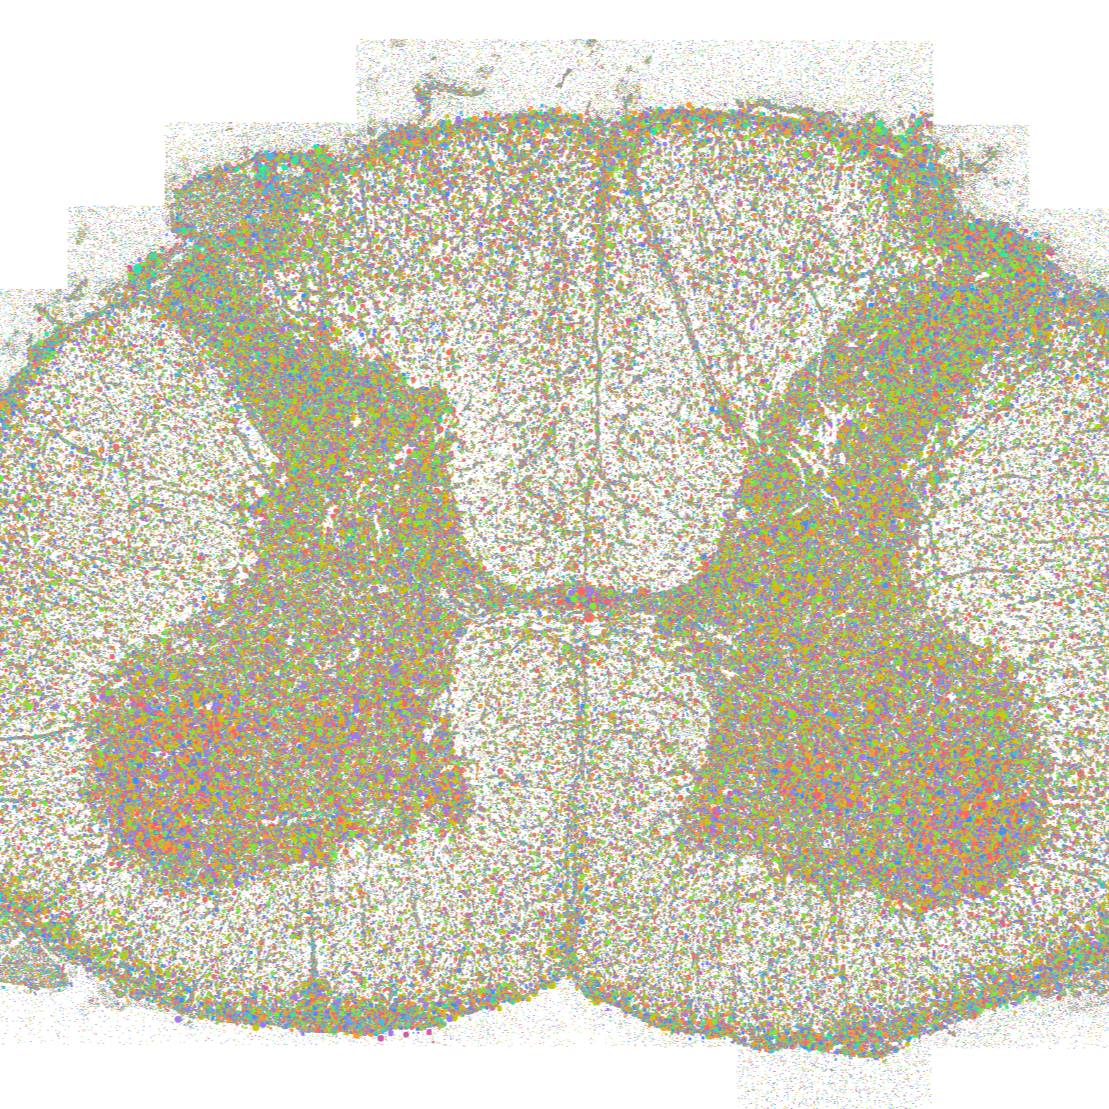

Xenium spatial transcriptomics of 8 human spinal cords.

Data Collection: Spatial transcriptomics data were generated from lumbar spinal cords of 12 human donors using 10X Genomics Xenium platform.

Experimental Design: Human lumbar spinal cord samples were processed following the 10X Genomics Xenium protocol without deviation. For improved segmentation accuracy, QuPath v0.4.4 was used to interactively outline individual cells expressing neuronal transcripts with no non-neuronal transcripts using the polygon tool to generate high-fidelity cell boundaries. Curated objects were exported as GeoJSON, and regions of interest were reintegrated into Xenium data by running the Xenium bundle through the import-segmentation pipeline in Xenium Ranger 3.1.1. Data processing and downstream analysis were performed using Xenium Ranger and Seurat package, enabling robust integration, clustering, and cell type annotation across samples. Eight major cell types were identified: neurons, lymphocytes, microglia, fibroblasts, oligodendrocytes, endothelial cells, ependymal cells, and astrocytes. Single-nucleus sequencing neuronal clusters were mapped into space using top expressing gene markers.